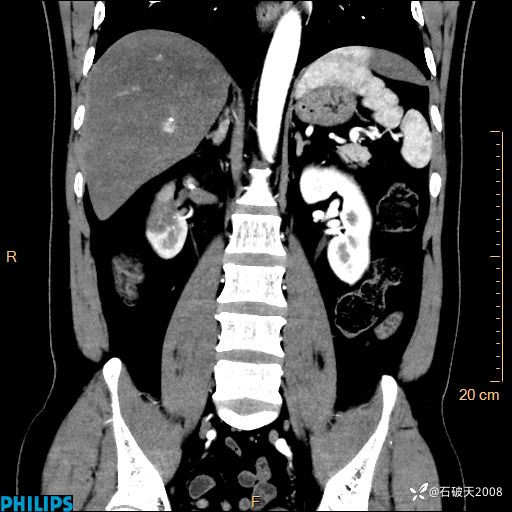

平扫轴位

增强轴位

冠状位